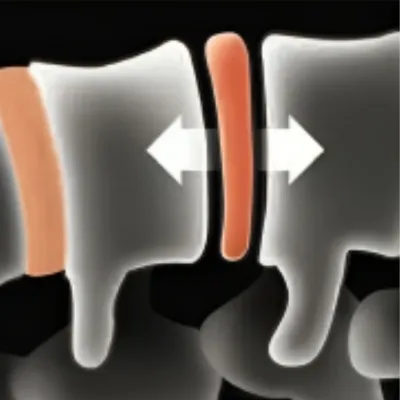

Our Advanced Laser-Enhanced Spinal Decompression™ Therapy is designed to gently stretch the spine, creating negative pressure within the discs. This process encourages the retraction of bulging or herniated discs and promotes the influx of healing nutrients, reducing inflammation and pain. Our unique methods relieve tension and pressure on the spinal discs, moving the affected parts of the spine back to their natural position. Additionally, the increased blood flow introduces more nutrients to the discs, promoting healing from within and significantly improving patient outcomes.

1) Creates space between vertebrae

2) Allows disc to regain volume

3) Allows disc absorption of gelatinous core

4) Reduces pressure on nerves